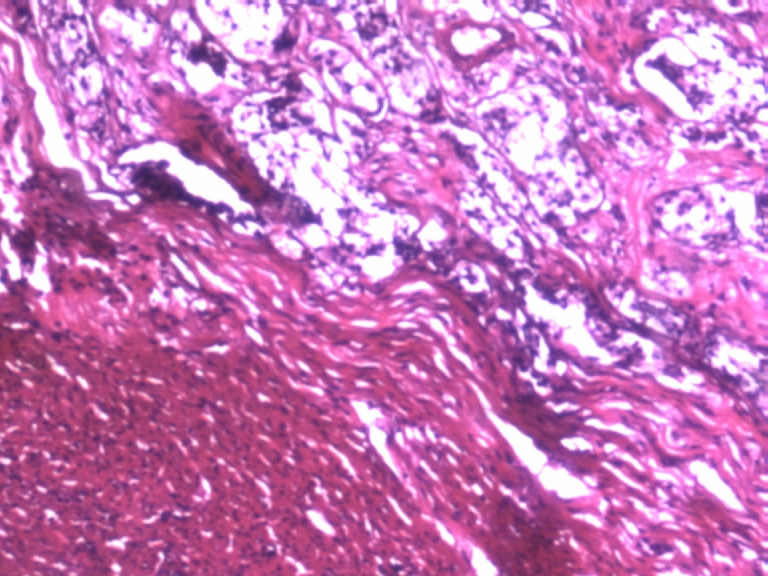

男,50岁,阑尾长7厘米,直径0.4---0.6厘米。剖开:尖端看见淡黄色区,不规则,界限欠清,0.15*0.2厘米,质中。

×参考诊断

考虑阑尾类癌

制片质量需要提高,恕我直言喽。

看不太清楚,有些结构有点像类癌。

是照片太亮了

需要酶标确诊,上传图片不太清楚